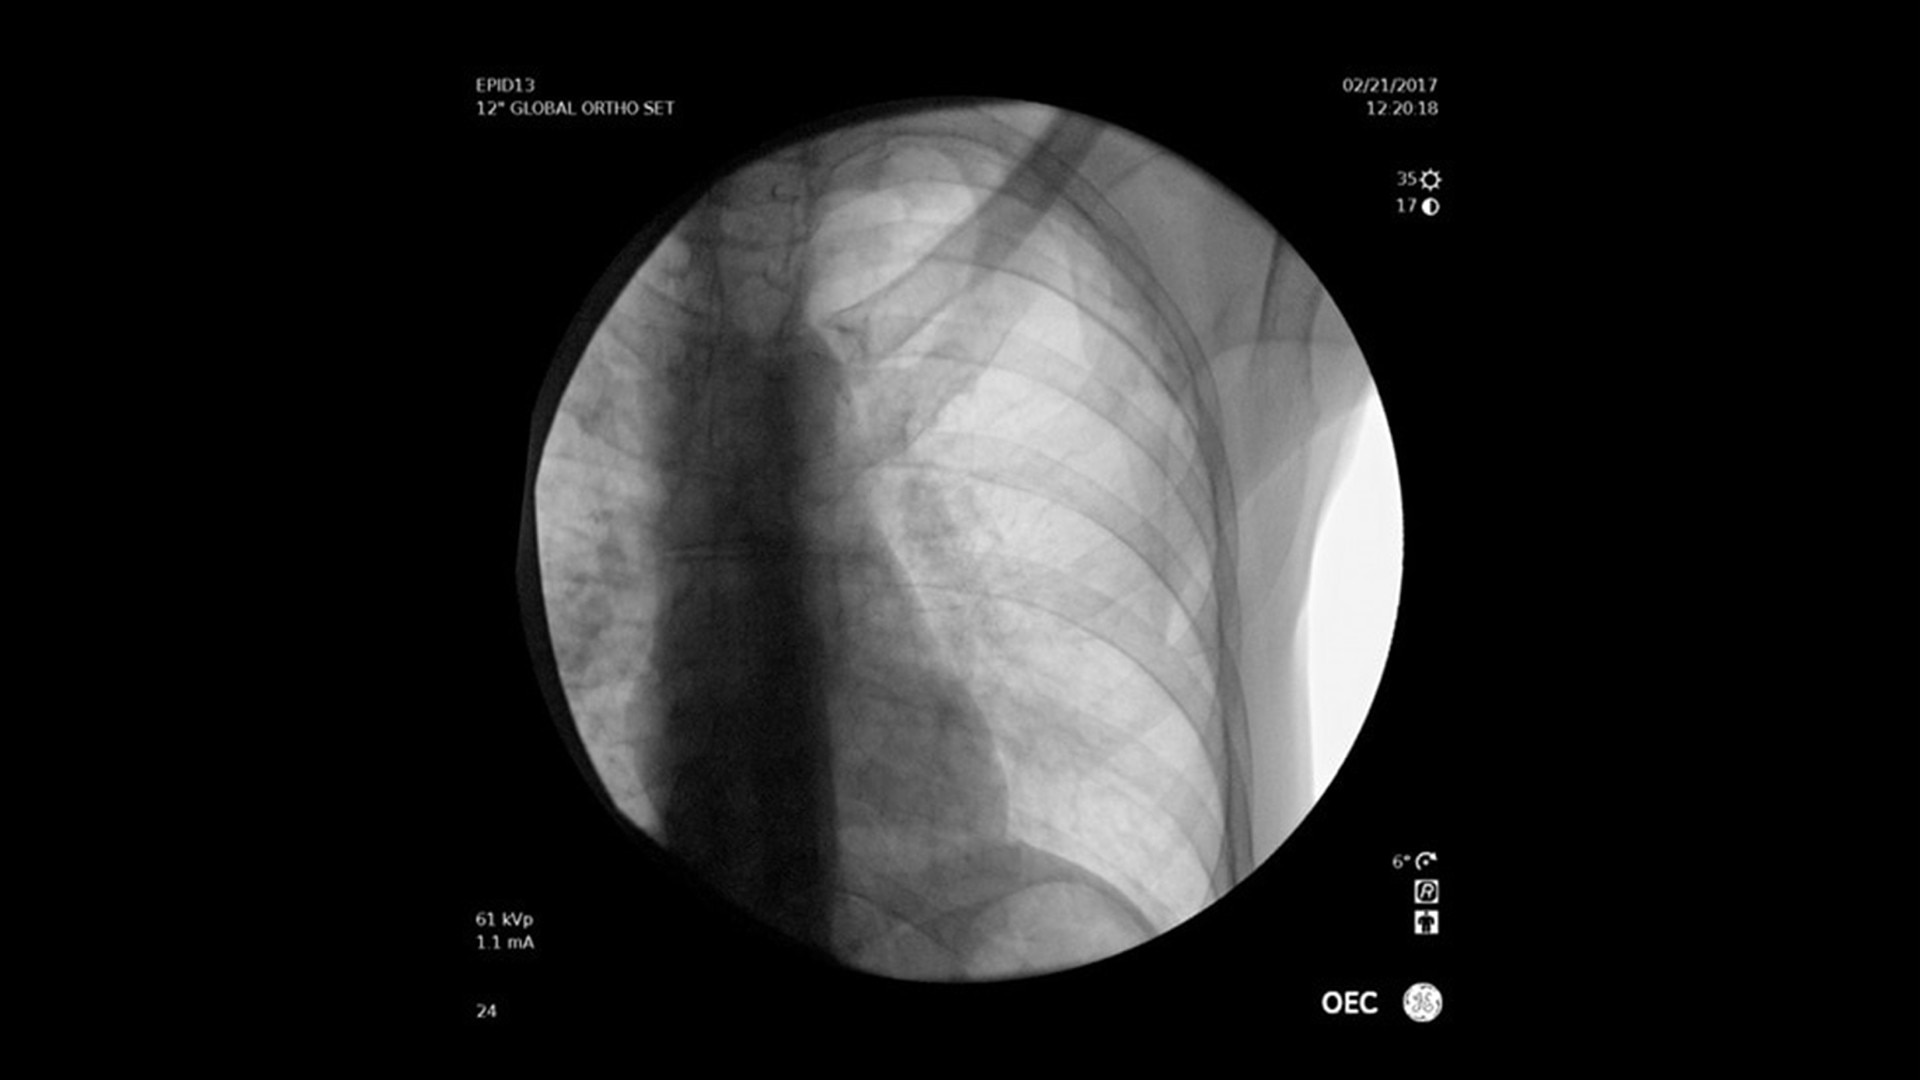

• Hervorragender Bildqualität für präzise intraoperative Entscheidungen

Vielseitig einsetzbar – ideal für orthopädische, gastrointestinale, endoskopische, urologische, neurologische und vaskuläre Eingriffe sowie für die Intensiv- und Notfallmedizin.

Der OEC Elite unterstützt Ihr OP-Team mit fortschrittlicher Bildverarbeitung, die sich dynamisch an klinische Anforderungen anpasst. So entstehen jederzeit präzise und detailreiche Bilder.

Renommierte Bildgebung – mehr sehen, mit weniger Dosis.

Nutzen Sie innovative Funktionen wie Live-Zoom, Digital Pen und vorkonfigurierte Bildprofile – darunter Pädiatrie, General HD und die optionale Bolus-Verfolgung – für eine präzise und schonende Bildgebung.